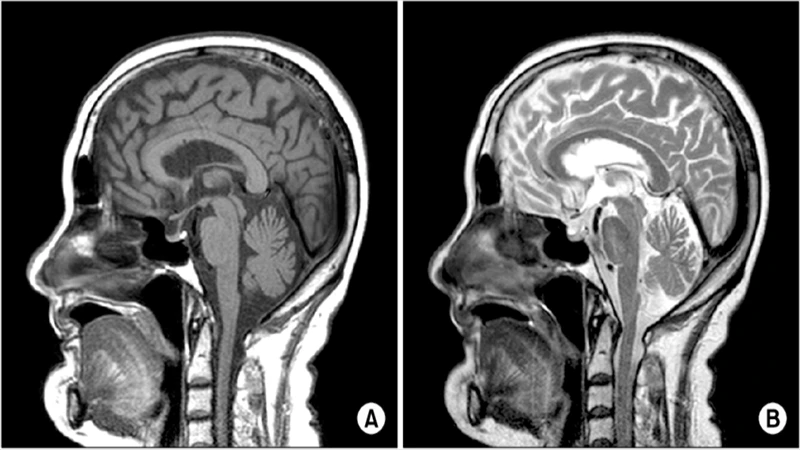

T1-Weighted (The "Anatomy" Sequence)

The T1-weighted sequence is the workhorse for visualizing normal anatomy. It provides excellent contrast between different soft tissues, making it easy to distinguish gray matter from white matter in the brain, for example.

- Key Characteristic: Fat is bright, and water (like cerebrospinal fluid, or CSF) is dark.

T2-Weighted (The "Pathology" Sequence)

The T2-weighted sequence is extremely sensitive to changes in water content. Since most pathologies—such as tumors, inflammation, infection, and trauma—involve an increase in water (edema), they will appear bright on a T2 image.

- Key Characteristic: Water and fat are both bright.